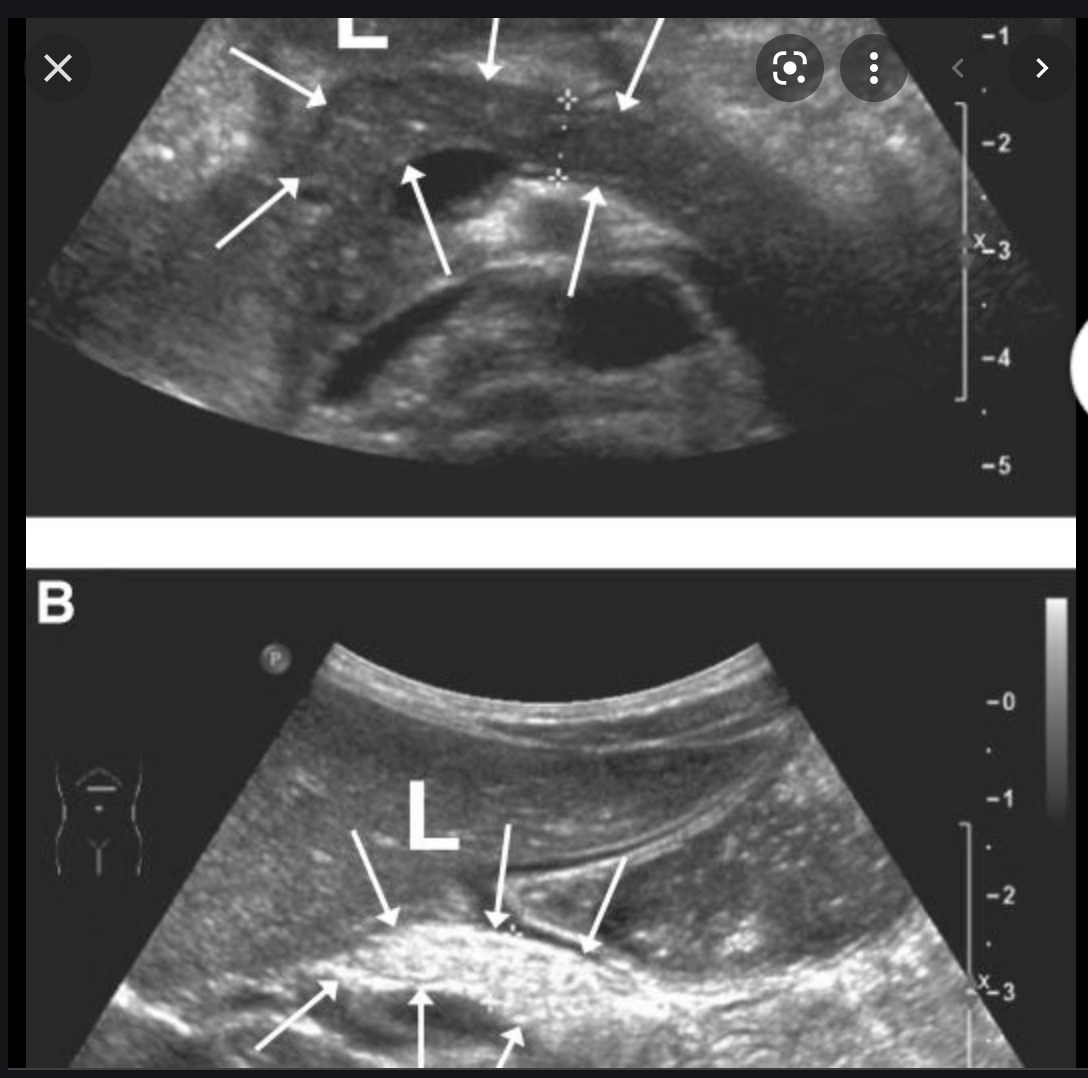

Single phase CT scan (multiphase scans not performed due to age of patient) demonstrates a diffusely enlarged pancreas with a “halo” like rim of hypoattenuating tissue which is smoothly marginated. Minimal peripancreatic fat stranding.

Associated splenic vein thrombosis, splenomegaly and cavernous transformation of the portal vein.